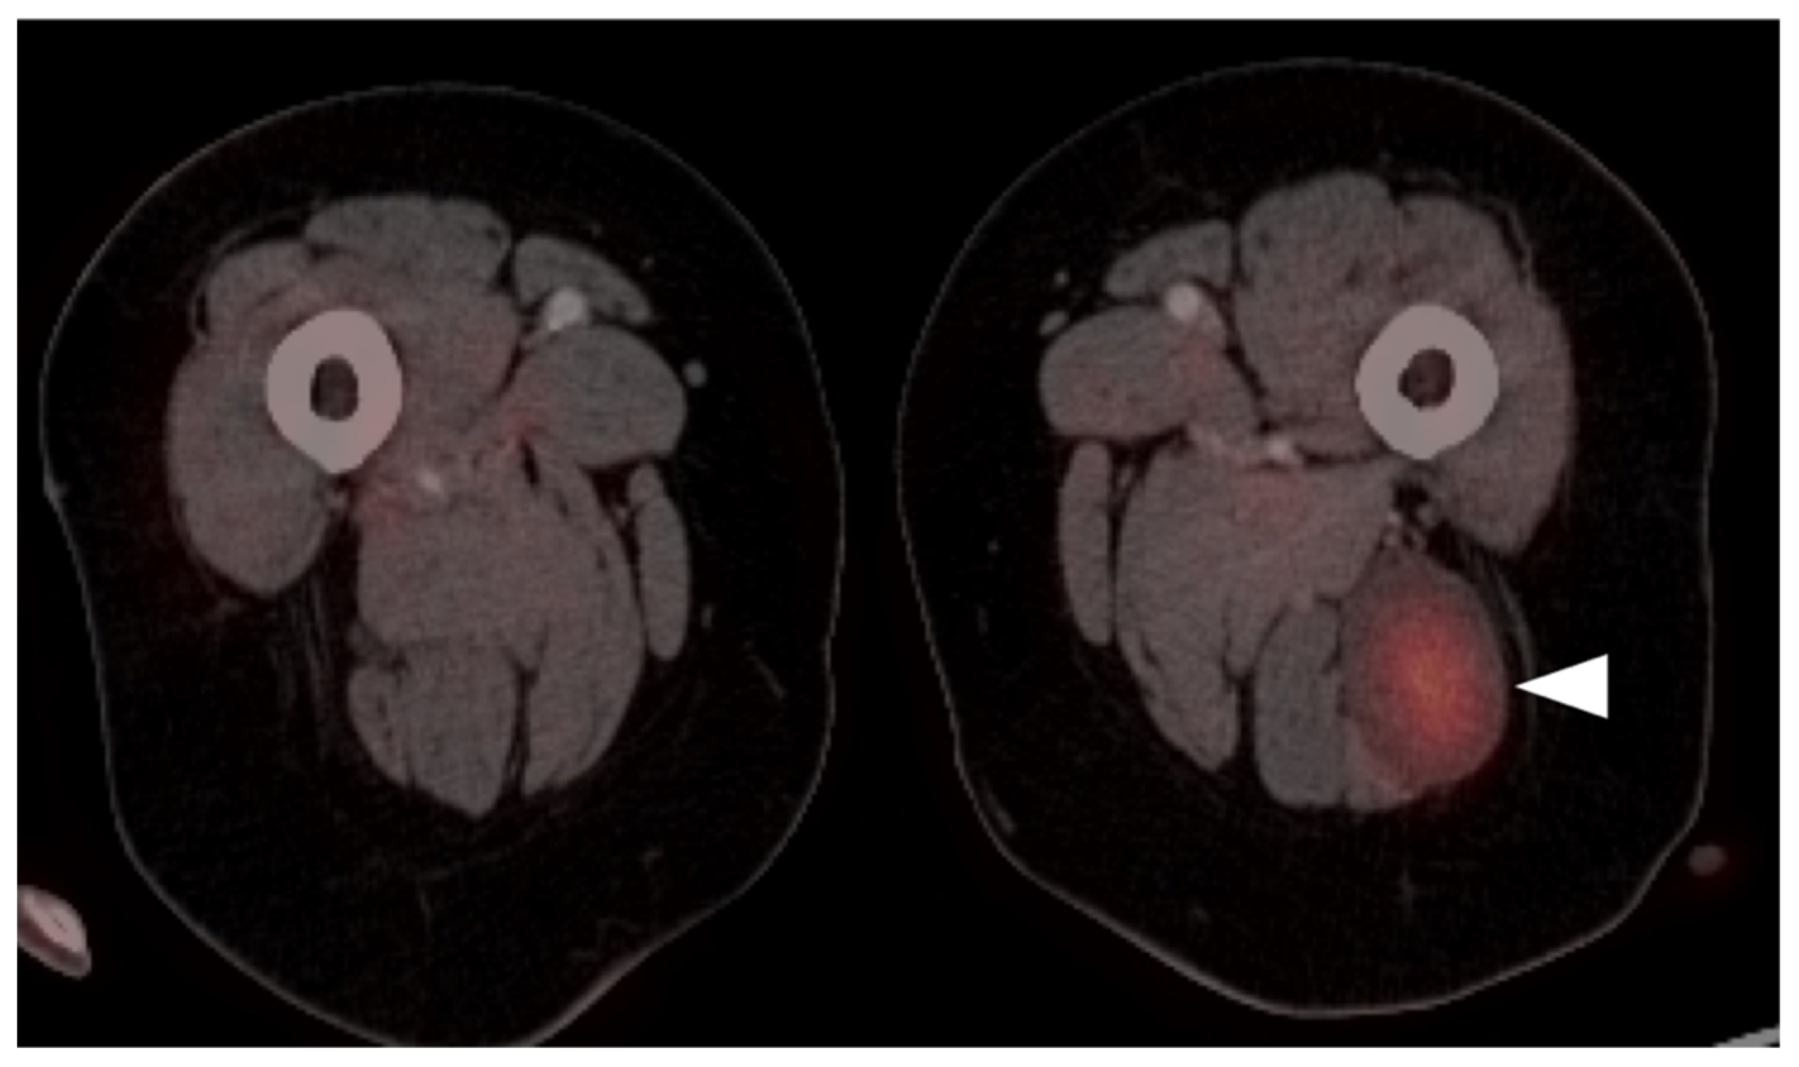

3.1.8. Nerve Sheath Tumors

3.2. Bone Sarcomas

3.2.2. Osteosarcoma

3.2.3. Ewing Sarcoma